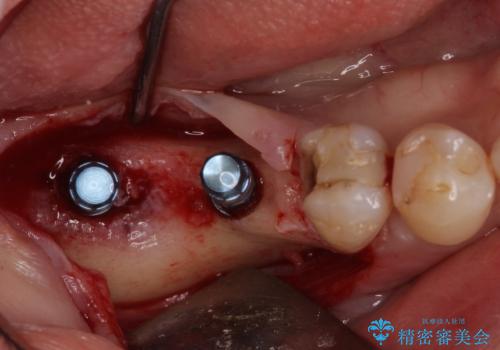

診察したところ、前歯は反対咬合であり、その影響で抜歯が必要な奥歯があることが分かりました。

抜歯が必要な奥歯は、インプラント並びにブリッジにより補綴を行い、上下前歯は反対咬合を改善させるように補綴治療を行うこととしました。